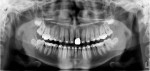

A panoramic radiograph and four bitewing intraoral radiographic projections were made (Figure 1 and Figure 2). The panoramic radiograph showed an open apex of tooth No. 18 and increased trabecular density in the interproximal area between teeth Nos. 18 and 19. Developing maxillary and mandibular third molars were also observed on the panoramic radiograph. Bitewing radiographs did not exhibit any significant periodontal bone loss. These 2-dimensional radiographic images provided non-significant radiographic findings that could not explain the patient's clinical findings.